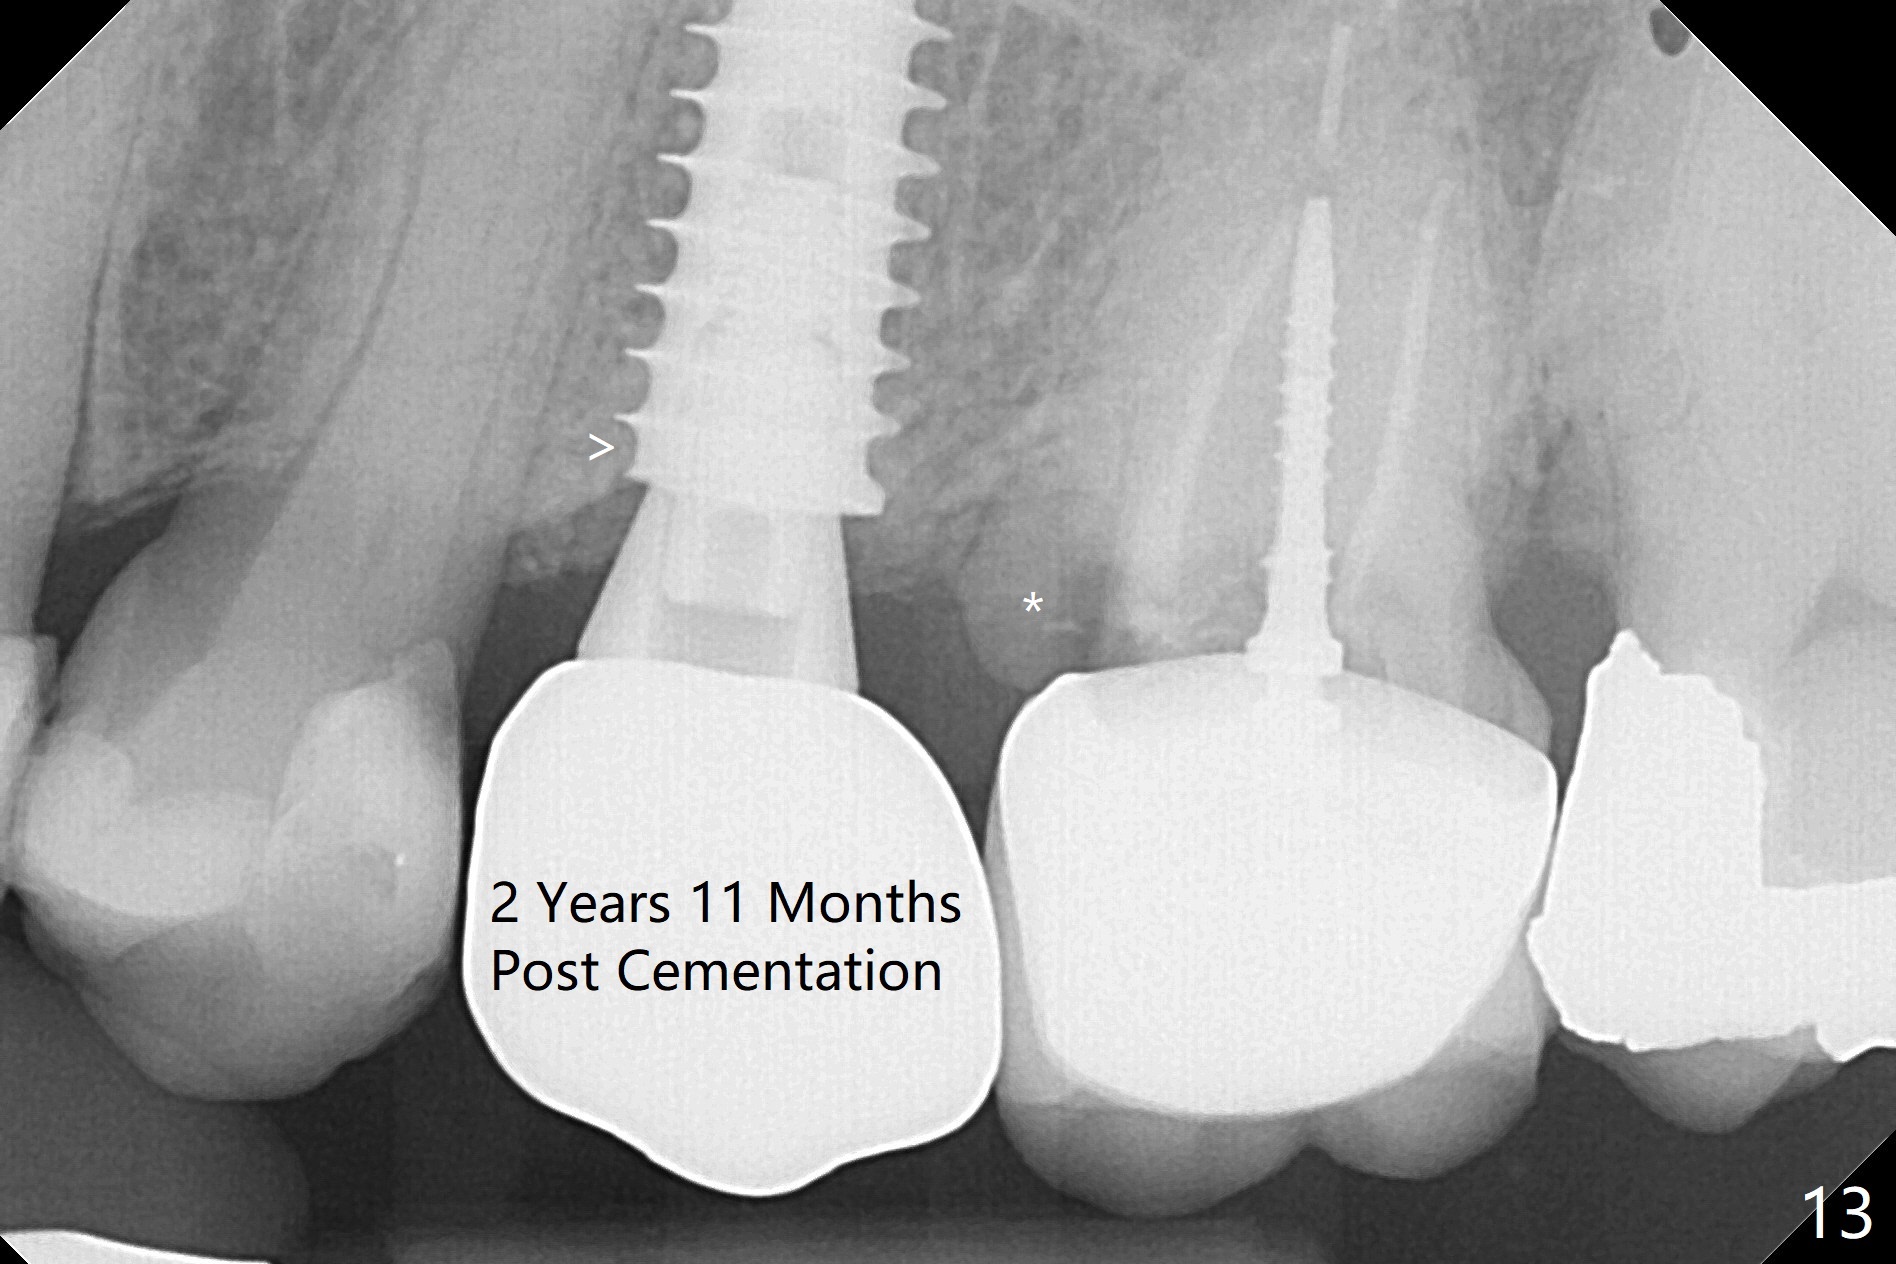

Since the apical native bone is limited at #13 after extraction, no PA is taken until a 4x11 mm dummy implant is placed after 1.6 mm and 3.3 mm drills for 13 mm (Fig.1). After using Lindamann bur to move the osteotomy distal and reusing 3.3 mm drill, the trajectory of a 4.5x11 mm IBS dummy implant improves (Fig.2,3 with low stability). When the implant is removed, the buccal portion of the socket is found to be perforated (Fig.4 P). Although the reason for the perforation is unknown, it is repaired by insertion of a piece of PRF plug, followed by allograft. #1 and 2 in Fig.4 represent the 1st and 2nd osteotomies, as shown in Fig.1 and 2, respectively. The trajectory of the final 5x13 mm implant is acceptable (Fig.5-7, different angulations), so is insertion torque (45 Ncm). After placing a 5.5x4(4) mm abutment, an immediate provisional is fabricated (Fig.8 P) with occlusal clearance (*). The interdental papillae remain in place 12 days postop (Fig.9 *). There is no sign of postop sinus infection. The provisional is loose 18 days postop; the abutment is changed to 5x4(3) mm (Fig.10). It is difficult to catch the mesial margin of the abutment for impression 4 months postop, due to poor oral hygiene and the short cuff (3 mm, Fig.11). The appointment for impression is rescheduled with emphasis on oral hygiene and no wearing the provisional for a few days prior to next appointment. Bone has grown into the space between the 1st and 2nd threads 5 months post cementation (Fig.12) and the bone is normal, solid and dense 2 years 11 months post cementation (Fig.13 >). There is mesial open margin of the tooth #14 (Fig.13,14 *).